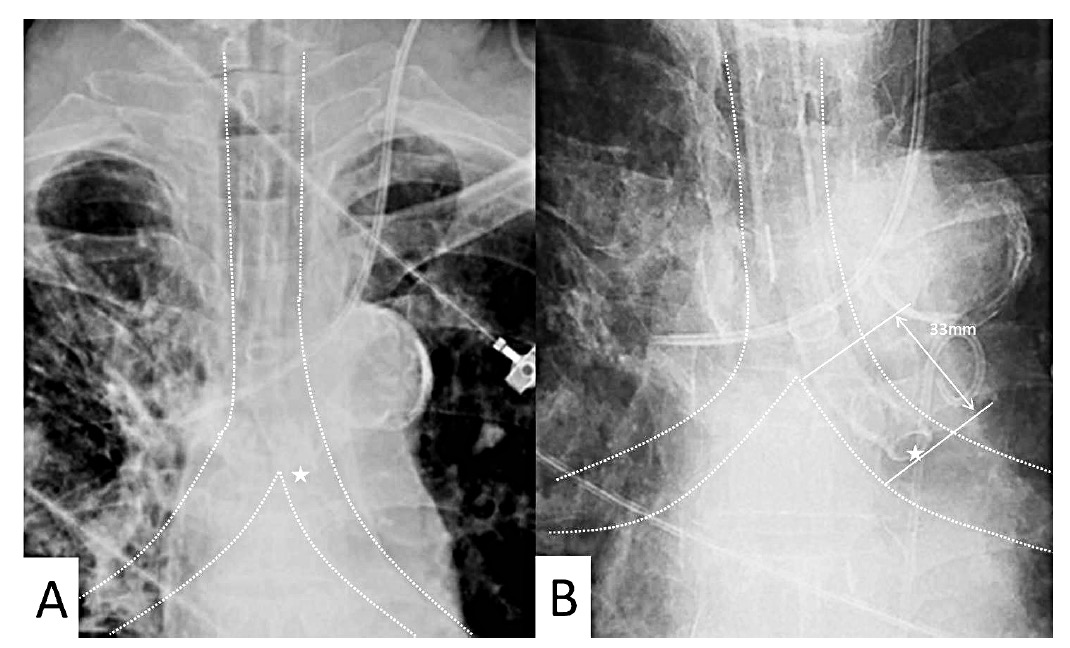

Endotracheal Tube Radiopaedia . anteroposterior chest radiograph shows endotracheal tube tip (arrow) in right main bronchus, resulting in complete. A malpositioned endotracheal tube is a potential hazard to the intubated patient. endobronchial intubation is the not infrequent finding of the endotracheal tube located in a bronchus and is a trivial diagnosis to. endotracheal tubes (etts) are used in children with acute respiratory distress or who need anesthesia, and tracheostomy tubes are used in children with prolonged respiratory compromise. Chest radiographs are routinely used to assess ett and tracheostomy tube position.